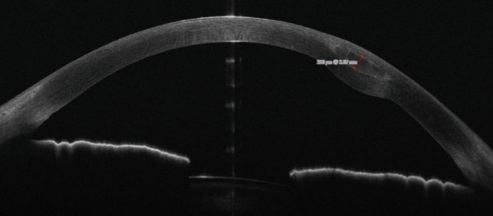

Preoperative evaluation commonly involves measurement of uncorrected and corrected distance visual acuity (UDVA and CDVA), slit-lamp examination, corneal topography/tomography including keratometry values such as Kmax and Kmean, and anterior segment optical coherence tomography (OCT).[1][12][13]

Channels are created using a Femtosecond laser or manual dissection. Depth of the channel is more commonly determined by going 35-70% depth of total cornea thickness.[12] There are also reports of going a fixed depth(i.e. 250 um) from the corneal surface.[5][13] The entry incision is on the steep axis or superiorly. The second incision is often 180 degrees from the first. Channel creations can range from an inner diameter of 4-6.5 mm to an outer diameter of 6.1-8mm.[12] Ranges can be based on scotopic pupil size and location of the cone as determined by OCT elevation tomography.[13]

Postoperative monitoring typically involves topography/tomography and anterior segment OCT to assess corneal shape changes and segment positioning. UCVA, CDVA, Kmax, and Kmean can be re-evaluated as well to track visual and refractive outcomes.[11][9][14][16]